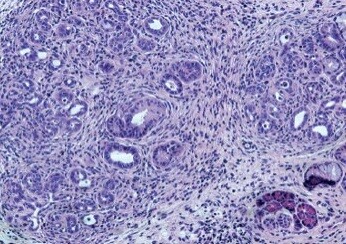

Pancreatic ductal adenocarcinoma (PDAC) has been connected to the presence of Porphyromonas gingivalis, a prevalent anaerobic bacterium known for its association with periodontal disease. Leveraging epidemiological clues, Professor Gabriel Nussbaum’s team at the Institute of Biomedical and Oral Research, based at The Hebrew University of Jerusalem, embarked on a journey to elucidate the potential of P. gingivalis in driving the progression of one of the deadliest forms of cancer.

The team’s research entailed a comprehensive examination of P. gingivalis translocation from the oral cavity to the pancreas using mouse models. By introducing the bacterium to genetically engineered mice predisposed to PDAC, they uncovered compelling evidence of accelerated cancer development, which they have published in the journal Gut.

Key findings from the study indicate that viable P. gingivalis was found in the pancreas of healthy mice after applying it to the gums, and prolonged exposure caused changes in the pancreas, affecting its microbial balance. Additionally, applying P. gingivalis orally sped up the progression from early pancreatic abnormalities to pancreatic cancer in mice with a specific genetic mutation. The research also showed that this genetic mutation helped P. gingivalis survive inside cells, and the bacteria supported the survival of pancreatic cancer cells even when conditions were tough. The team’s discoveries emphasise a direct link between P. gingivalis and the development of pancreatic cancer in mice, offering significant insights into how this disease progresses.